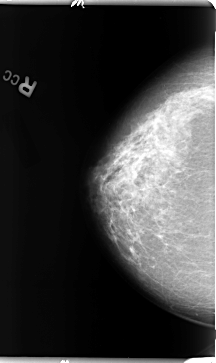

B_3096_1.RIGHT_CC

LEFT_CC LINES 4736 PIXELS_PER_LINE 2624 BITS_PER_PIXEL 12 RESOLUTION 50 OVERLAY

FILE: B_3096_1.LEFT_CC.OVERLAY

TOTAL_ABNORMALITIES 1

ABNORMALITY 1

LESION_TYPE MASS SHAPE IRREGULAR MARGINS OBSCURED

ASSESSMENT 3

SUBTLETY 2

PATHOLOGY BENIGN

TOTAL_OUTLINES 1